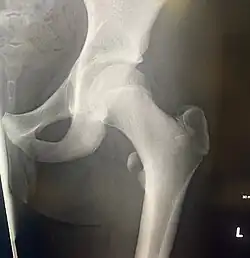

In human anatomy, the lesser trochanter is a conical, posteromedial, bony projection from the shaft of the femur. It serves as the principal insertion site of the iliopsoas muscle.[1]

The lesser trochanter is a conical posteromedial projection of the shaft of the femur, projecting from the posteroinferior aspect of its junction with the femoral neck.[1]

The summit and anterior surface of the lesser trochanter are rough, whereas its posterior surface is smooth.[1]

The intertrochanteric crest (which demarcates the junction of the femoral shaft and neck posteriorly) extends between the lesser trochanter and the greater trochanter on the posterior surface of the femur.[1]

The lesser trochanter can be involved in an avulsion fracture.[4]